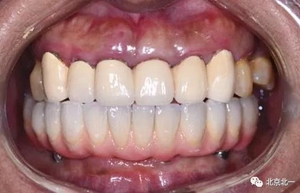

圖二十:永久修復(fù)咬合關(guān)系

圖二十一:半年后復(fù)查X片